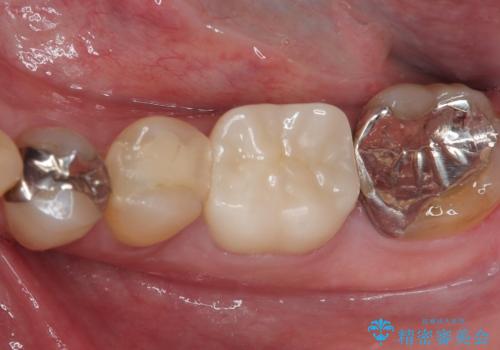

根管治療を実施した後に、フルジルコニアクラウンにて補綴することとしました。

大臼歯の治療後に海外赴任され、数年ぶりに帰国されました。

奥歯に痛みがあるとのことで診察を行ったところ、海外(アメリカ)にて処置をした手前の歯が既に失活していることが分かりました。なお、治療を行った大臼歯はレントゲン写真上の治癒が認められました。

症状のあった歯に対しても根管治療を行い、同様に補綴治療を行いました。